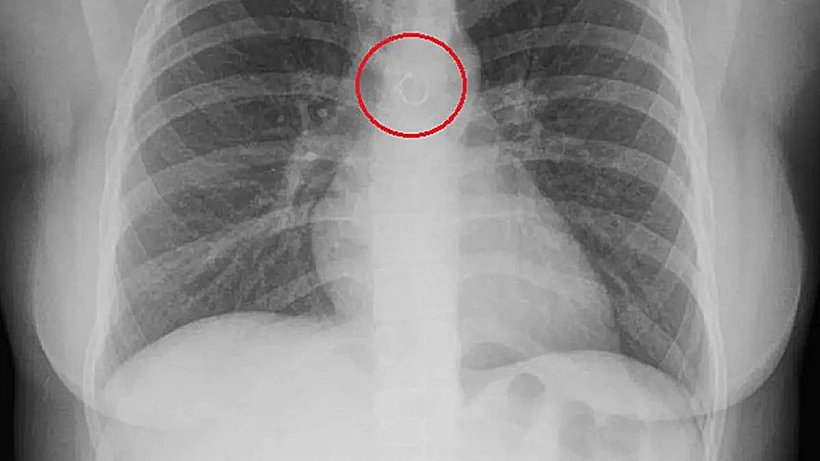

צעירה בת 26 ממקסיקו פנתה לרופאים אחרי חודש של שיעול שלא עבר. צילום החזה שעברה חשף ממצא חריג במיוחד: העגיל מהמחיצה שהיה באפה לא אבד סתם, אלא נשאף בשוגג והגיע כמעט עד כלי דם מרכזי בבית החזה שלה

מדובר במוניקה דיאנירה קבררה בראחאס, צעירה מקסיקנית בת 26, שסבלה במשך כחודש משיעול מציק שלא חלף. כשהגיעה לבדיקה, היא ציפתה שצילום החזה שעברה יגלה את מקור הבעיה, אבל לא העלתה בדעתה שהממצא יהיה הספטום (עגיל הנעוץ במחיצת האף) שלה. רק אז התברר שהעגיל שהיה באפה נעלם, וככל הנראה לא נפל סתם - אלא נשאף פנימה בשוגג בזמן שישנה.

קבררה בראחאס סיפרה כי התיאוריה היחידה שהצליחה לגבש היא שאחד הסוגרים המתכתיים של העגיל השתחרר בזמן שישנה על הגב, הטבעת החליקה לגרון, ומשם נשאפה אל דרכי הנשימה. היא מספרת שזו הייתה גם ההשערה שהציגה לרופא הריאות. ההלם הראשוני, לדבריה, התחלף מהר מאוד בפחד ממשי על חייה, במיוחד אחרי שנאמר לה שהעגיל נמצא במרחק זעיר במיוחד מאבי העורקים.

צילום הרנטגן של הצעירה | צילום: רשתות חברתיות